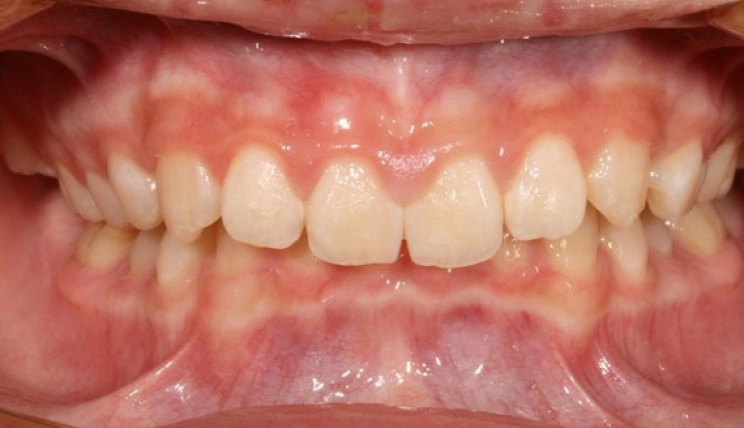

Generally Straighter Teeth

Some smiles don’t have anything “wrong” with them at all — but small fixes can make a big difference in a patient’s life. With Invisalign® treatment, your patients can now get a smile they’ll love up to 50 percent faster. 1 2

Patient Information:

Age: 62

Gender: Female

Invisalign Treatment Option: Invisalign Comprehensive

Total Treatment Time:

13 months